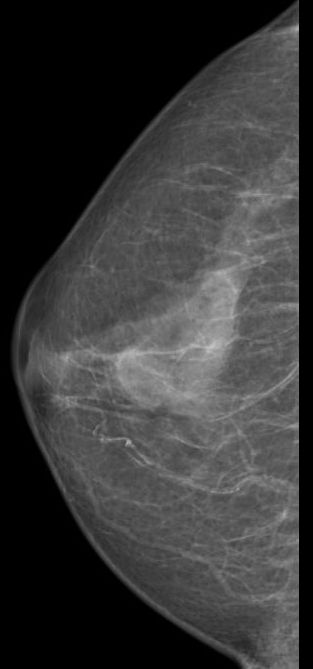

| Mammographie | 76-jährige Patientin mit multiplen Metastasen in Wirbelsäule und Leber. Zunächst kein Tastbefund der Brust. Dann suspekter Tastbefund rechts oben außen paramamillär. Mammographie zunächst o.B. befundet. Stanzbiopsie rechts oben außen: lobuläres Karzinom. | |||||||||